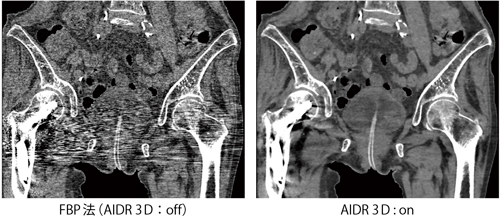

filtered back projection(FBP)法とAIDR 3Dの比較画像を示す(図2)。FBP法では,大腿部に挿入された金属より発生するストリークアーチファクトにより,骨盤内臓器の形状把握が困難であるが,AIDR 3Dを用いて画像再構成を行うことにより,ストリークアーチファクトが大幅に軽減され,骨盤内臓器の形状が把握しやすくなっている。

図2 自然呼吸下・体動抑制不能・上肢挙上不能例におけるAIDR 3D 臨床画像例

(データご提供:藤田保健衛生大学病院様)